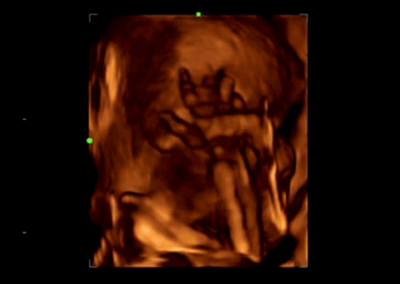

Z60

Sistema de diagnóstico ecográfico.

El sistema Z60 es una buena opción para aquellos que requieren un rendimiento de imagen de alta calidad, una movilidad simple y asequibilidad cuando se trata de imágenes ecográficas avanzadas. Con configuraciones completas y un diseño integrado, el Z60 es el resultado de los esfuerzos continuos y decididos de Mindray para hacer que la atención médica primaria sea más eficiente, eficaz y accesible para todos.